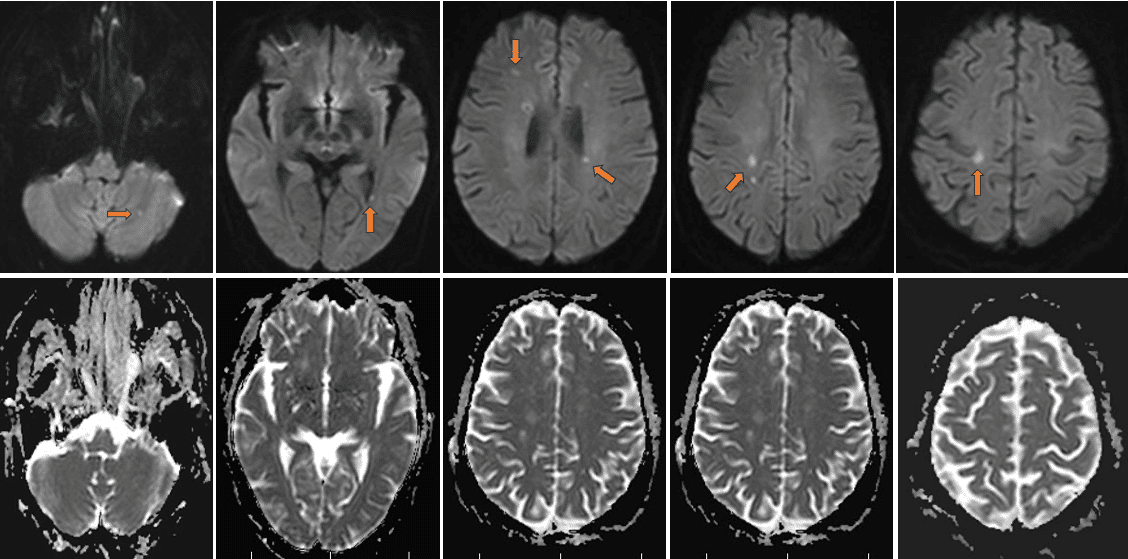

一、病例特点:患者靳x,女,急性起病;临床表现为言语不清伴肢体无力;既往有高血压、糖尿病病史;半年前发现左侧肺门、下肺占位,穿刺病理提示小细胞神经内分泌癌,给予依托泊苷联合顺铂化疗;查体:神志清楚,非流利性语言,简单对答尚切题;颅神经检查未见异常。双下肢肌力4级,肌张力略低。辅助检查:急查血常规(20240731): ★红细胞计数 3.02x10^12/L↓,★血红蛋白量 104↓g/L,★红细胞比积0.320↓,平均红细胞体积 105.6↑fL,平均红细胞血红蛋白量34.40↑pg;生化全项(20240731): ★尿酸 437↑μmol/L,★葡萄糖7.23↑mmol/L,★总胆固醇 6.01↑mmol/L,★甘油三酯 1.97↑mmol/L,★低密度脂蛋白胆固醇4.33↑mmol/L;肺癌标志物(20240731): 神经元特异烯醇化酶 19.10↑ng/mL;二、神经影像:上图为头MRDWI、ADC序列(2024-8-2 本院)可见左侧小脑、左侧脑室后角旁、双侧侧脑室周围白质、右侧放射冠区及右侧额叶弥散信号异常,信号高低不一,提示病灶形成时间不同;ADC序列相应部位或不明显、抑或成低信号。三、临床印象特鲁索综合症(Trousseau syndrome) PS:特鲁索综合症(Trousseau syndrome)是一种副肿瘤综合征,主要表现为恶性肿瘤相关的神经系统病变。在特鲁索综合症发生的情况下,恶性肿瘤会激活患者体内的凝血系统,从而造成系统性血栓和脑梗死。临床以处理基础病及抗凝治疗为主!Tips 心情驿站